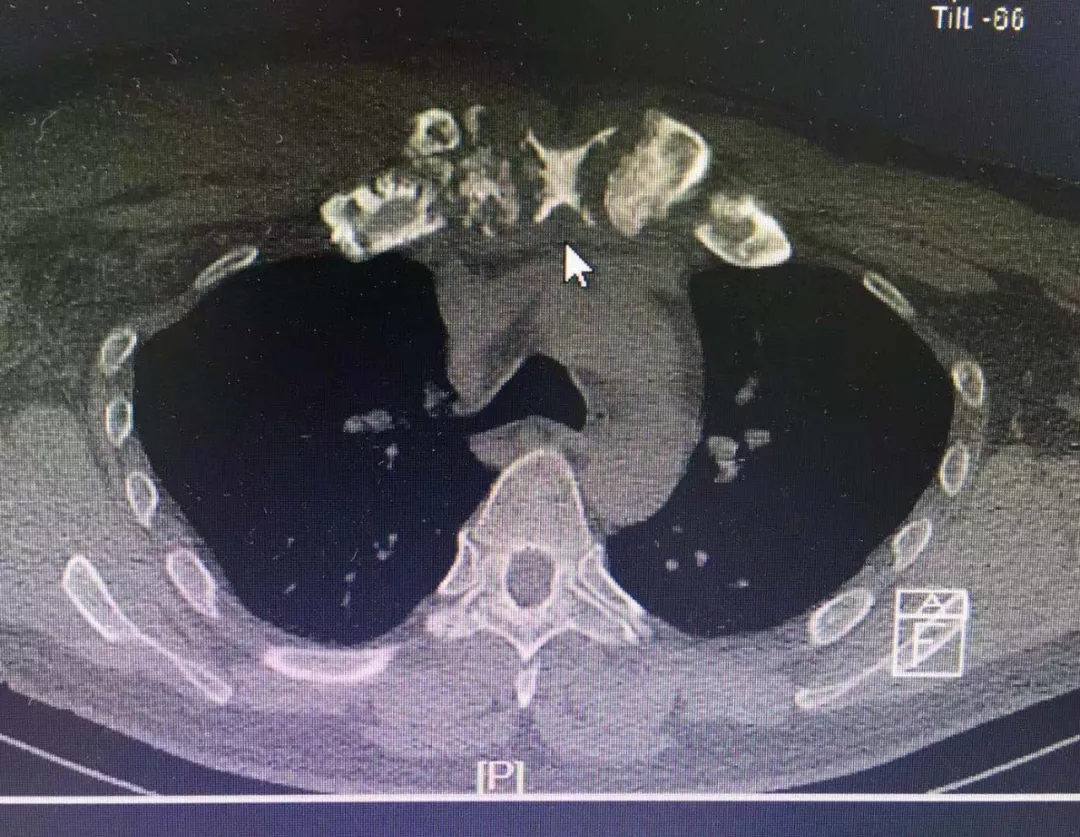

术前(图一)炎性损毁的胸骨、双侧锁骨和第一肋骨

患者男,44岁,患慢性胸骨并双侧锁骨及第一肋骨骨髓炎迁延三年有余,曾历经两次手术均未能治愈,于2019年7月18日收入我院胸外科。经检查证实:病变已成慢性骨髓炎改变,且与之前相比,病变已逐渐加重,范围累及胸骨大部以及双侧锁骨和双侧第一肋骨。胸外科陈钢主任与本院骨科、影像科等主任和医师们经过充分的讨论研究后认为:再次彻底手术,进行大范围的病灶扩创+胸壁重建是解除患者病痛的唯一选择。